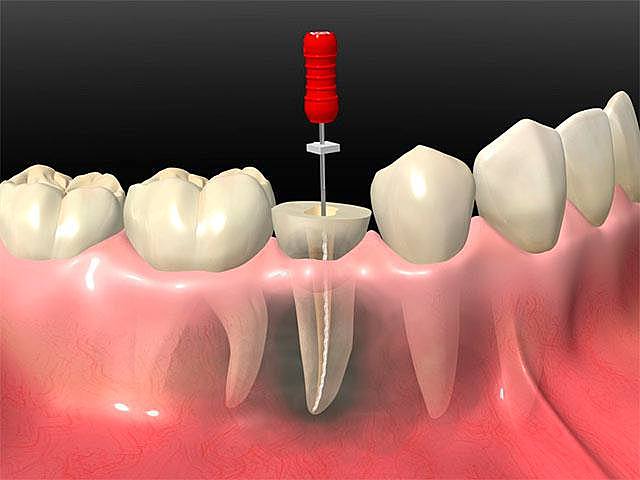

• Endodoncia.

Endodoncia.

Endodoncia OD. 3.5

Referir endodoncia OD. 2.6 y 3.7